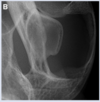

98

“Maxillofacial injuries and diseases that cause an open mouth in cats”. Constantaras & Charlier. JVD 2014. given this radiograph, what is the most common cause of the open jaw locking and abnormalities on DV radiograph?

right rostrodorsal TMJ luxation